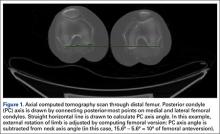

We used the software tool to draw the femoral neck axis. From the end of this line, a straight horizontal line is drawn on-screen (Figure 3). The software calculates the angle formed—the femoral neck axis angle. We assigned a positive value for a femoral head that pointed anteriorly on the image and a negative value for a head that pointed posteriorly. Adjusting for external rotation of the limb involved calculating the femoral version by subtracting the PC angle from the neck axis angle; adjusting for internal rotation involved adding these 2 angles.